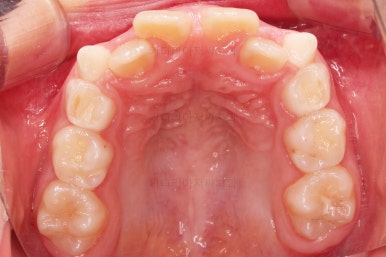

마찬가지로 초진 시 입안의 모습이에요.

아래 앞니가 윗니보다 앞에 있는 "반대교합" 즉, 거꾸로 물려있는 상황이었고요.

어금니 쪽을 보시면(왼쪽 위 사진) 윗니 어금니도 아래 어금니보다 안쪽으로 들어와 있는 "어금니 반대교합"도 있는 상황이었어요.

즉, 윗니가 있는 위턱뼈가 3차원적으로 작은 상황이었던거죠.

이렇게 아랫니들이 윗니보다 앞으로 나와있는 형태의 부정교합을 "앵글씨 3급" 부정교합이라고 합니다.